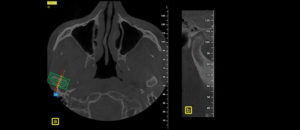

El objetivo del presente estudio fue evaluar los factores (referidos a la CBCT) que influyen en la toma de decisión en tratamientos para extracción de